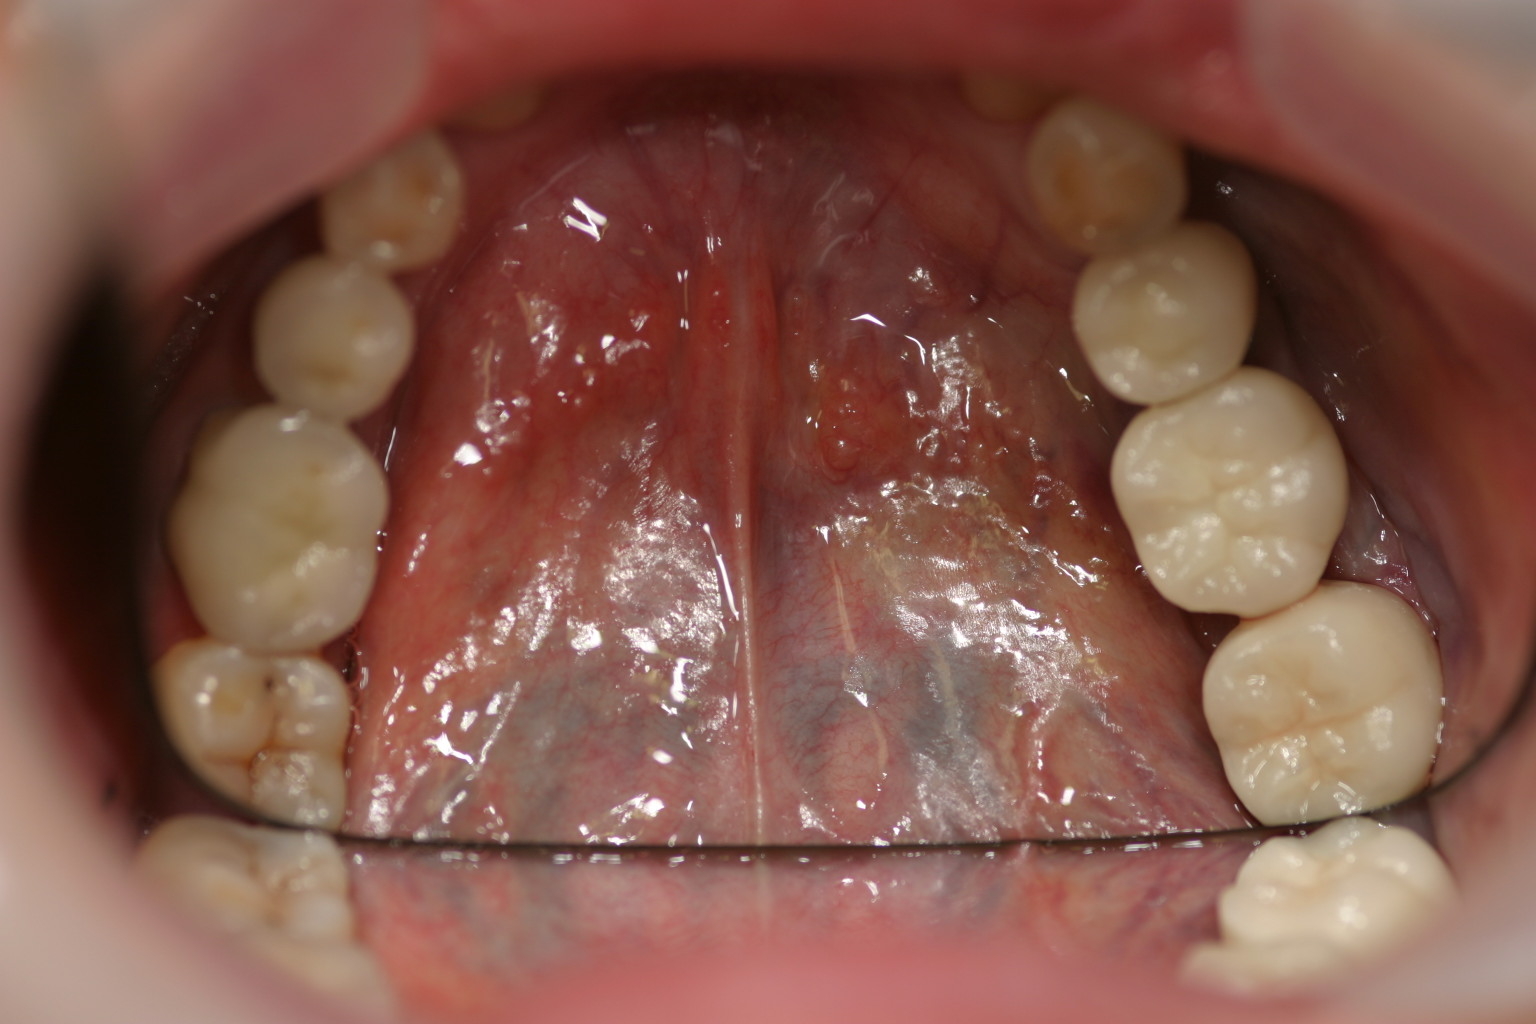

左下567番インプラントジルコニアアバットメント及びジルコニアセラミッククラウン装着